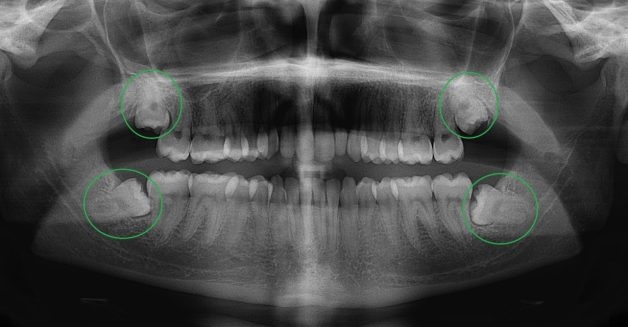

Răng khôn mọc lệch rất phổ biến và mức độ lệch ở mỗi người và mỗi răng là khác nhau

Do thời điểm mọc răng 8 là độ tuổi trưởng thành, khung xương hàm đã ổn định, không phát triển rộng hơn, hơn nữa xương lúc này có độ cứng cao nên răng 8 khó có thể trồi thẳng lên mà thường rơi vào tình trạng thiếu không gian, gây nên hiện tượng răng mọc ngầm, mọc chéo, đâm ngang, không như binh thường. Chính vì lý do đó mà răng 8 mọc lệch rất phổ biến và mức độ lệch ở mỗi người và mỗi răng là khác nhau. Có người chỉ mọc 1-2 trên tổng số 4 răng, thậm chí có người không mọc chiếc nào.